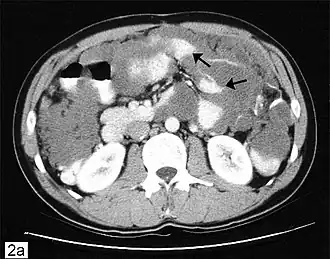

![]() Компьютерная томограмма брюшной полости с изображением псевдомиксомы брюшной полости с рассеянными перитонеальными массами (стрелки). | |